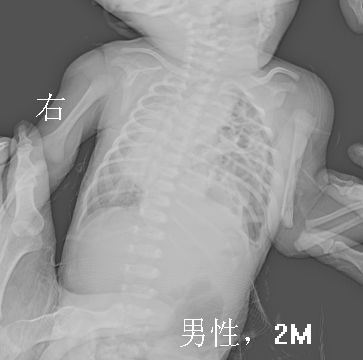

男性,2月,咳嗽半月。时有呼吸困难。血、尿、粪(-)

胸片显示左肺多发囊状密度减低区。

不排除左侧膈疝可能;建议行消化道造影检查。

纵隔及心影左移,考虑膈疝。

纵隔及心影右移,考虑膈疝,建议行消化道造影检查。